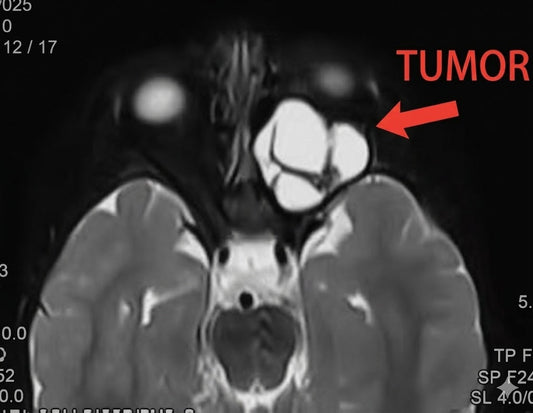

Diagnosis and Treatment of Rare Cardiac Conditi...

Mrs. Lim, a 58-year-old Malaysian patient, was initially misdiagnosed with idiopathic pulmonary arterial hypertension (IPAH). After a comprehensive diagnostic evaluation in Beijing, she was correctly diagnosed with a double-chambered right...